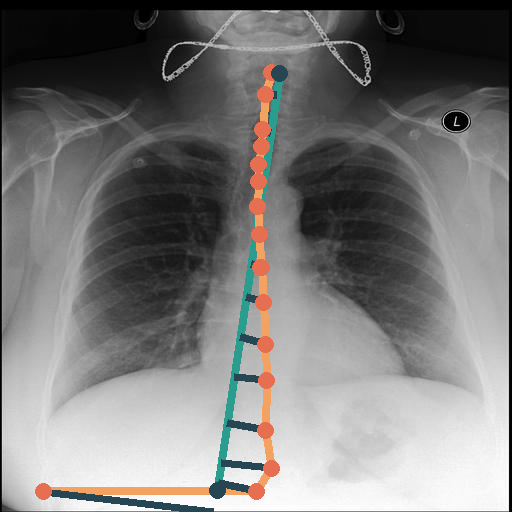

Automated Identification of the Center-Spine Distance via CXAS

We use all PA CXR from the MIMIC dataset and straightforwardly filter medical reports for the term scoliosis. We extract 2,054 images presenting scoliosis and 228,953 images not containing this phrase. We infer our CXAS model from all images and propose a spine-center distance (SCD) to measure the shift of the individual vertebrae. We calculate this by using the center point of the individual vertebrae segmentations. We then regress a centerline based on these vertebrae centers and compute the sum over the minimal distances of all vertebrae centers to the centerline.

In Fig. 4, we show qualitative examples of the calculation of the SCD for patients for the presence and absence of scoliosis. We can see that the vertebrae segmentation presents a noticeable curvature for the scoliosis case, leading to an SCD above 19, while for the patient with a healthy spine, the SCD is 1.125.

When conducting a t-test, we get a value of 35.30 (p-value 0.0001), indicating a statistically significant difference in SCD between positive and negative patients for scoliosis. On the left of Fig. 4, we show the distributions of the SCD in the form of violin plots for sex, age group, and pathology. Similarly to the CTR, SCD increases with age for the presence and absence of scoliosis. The results show that the older the patient gets, the less the disparity in mean SCD between scoliosis and no scoliosis becomes, indicating that the SCD becomes slightly less insightful the older the patient is. However, different from the CTR, the standard deviation of the SCD is considerably higher, and there is a relatively larger difference in means, leading to a higher predictive value for the identification of scoliosis.